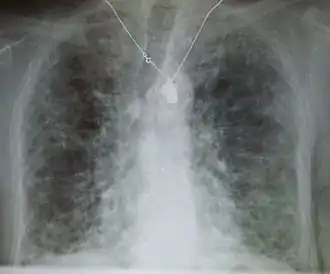

Рентгеновский снимок грудной клетки: фиброз легких, предположительно возникший вследствие приема амиодарона.